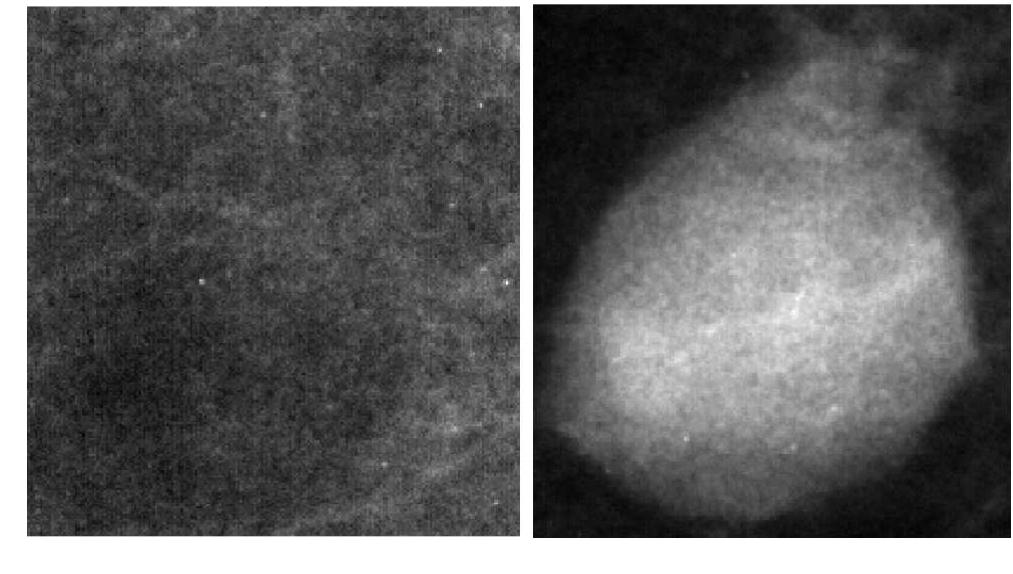

This paper presents a method for wavelet processing of mammogram images in order to highlight pathological changes which are important for diagnosing breast cancer. The method was used at the image pre-processing stage in a CAD (Computer... more

Breast cancer is the most widespread cancer in women. The life-time risk of a woman developing this disease has been established as one in eight. Currently mammography is a standard method and could decrease breast cancer mortality.... more

The proposed method focuses on the prediction of breast cancer in its early stage. It is very difficult to detect microcalcification due to its small size and low contrast with respect to the surrounding tissues. A new, fast and simple... more

In this article we present a classification system for an automatic detection of masses in digitized mammographic images. The systems consists in three main processing levels: a) image segmentation for the localization of regions of... more

Purpose of this work is the development of an automatic classification system which could be useful for radiologists in the investigation of breast cancer. The software has been designed in the framework of the MAGIC-5 collaboration. In... more